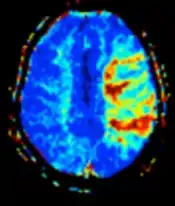

| Perfusion weighted (PWI) | Dynamic susceptibility contrast | DSC | Measures changes over time in susceptibility-induced signal loss due to gadolinium contrast injection.[23] |

|

|

Perfusion weighted

Perfusion-weighted imaging (PWI) is performed by 3 main techniques:

- Dynamic susceptibility contrast (DSC): Gadolinium contrast is injected, and rapid repeated imaging (generally gradient-echo echo-planar T2 weighted) quantifies susceptibility-induced signal loss.[45]

The acquired data is then postprocessed to obtain perfusion maps with different parameters, such as BV (blood volume), BF (blood flow), MTT (mean transit time) and TTP (time to peak).

In cerebral infarction, the penumbra has decreased perfusion.[24] Another MRI sequence, diffusion-weighted MRI, estimates the amount of tissue that is already necrotic, and the combination of those sequences can therefore be used to estimate the amount of brain tissue that is salvageable by thrombolysis and/or thrombectomy.